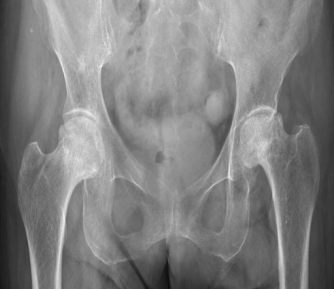

股骨头是髋关节的重要组成部分

在盆骨下方

大腿根部

起着承上启下的作用

股骨头坏死又称为股骨头缺血性坏死或股骨头无菌性坏死,指股骨头血供受损或中断,导致骨髓成分及骨细胞死亡及随后的组织修复,继而导致股骨头结构改变及塌陷,引起患者髋关节疼痛及功能障碍的疾病,是造成髋关节伤残的主要疾病之一。

股骨头坏死主要会引起三大明显症状

一、痛

骨头坏死了首要引起的就是痛,主要是胯、屁股、大腿根部疼痛,疼痛的程度会根据病情发展不断加重。

二、活动不灵活

股骨头坏死后,髋关节的活动也会不像原来一样灵活,尤其做内旋、外旋、屈曲这几个动作最明显。

三、骨骼变形

当股骨头坏死发展到比较严重的时候,股骨头甚至会塌陷,造成患肢缩短、骨盆倾斜等骨骼畸形。